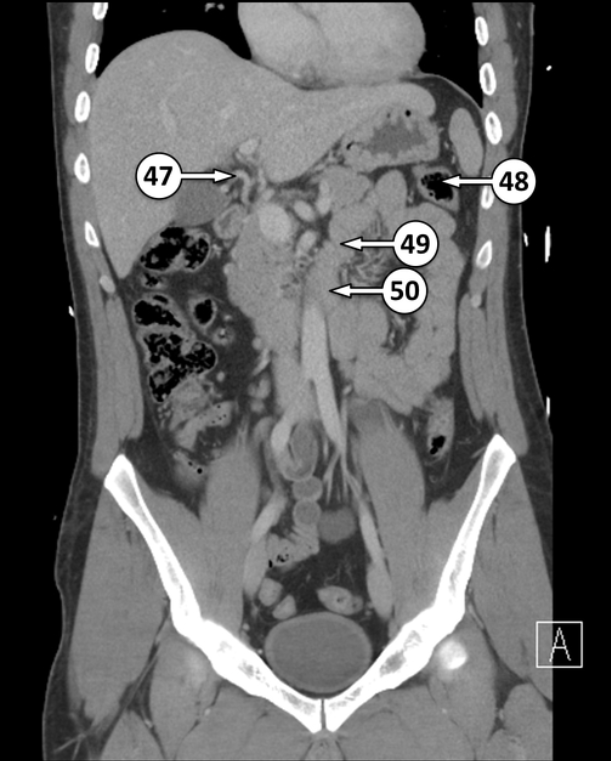

What artery is number 47?

Right hepatic artery

48 and 49 are flexures. Please label the different flexures

Splenic flexure

Duodenojejunal flexure